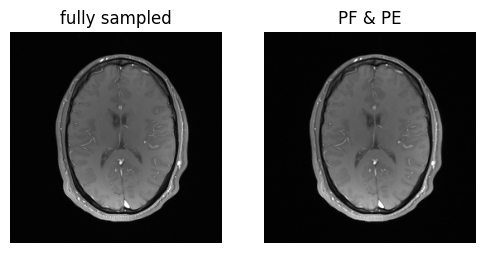

show_images(magnitude_fully_sampled, magnitude_pe_pf, titles=['fully sampled', 'PF & PE'])

../_images/d78db753b60ca62406efa3a2dd0649b7e39cecc9aef00870b725203c472c3750.png

That was easy! But wait a second — what about all these nice receiver elements of our coil?